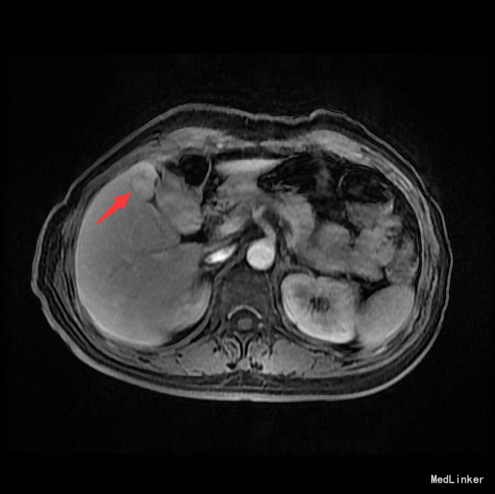

辅查:AFP 3.43ng/ml, CEA 1.47ng/ml。MR:肝S5段占位性病变(26*25mm),考虑肝癌可能性大,建议活检。

随访:术后病理示:(右肝肿物)送检肝组织部分呈结节状增生,结节间见粗细不等的纤维间隔,其内见血管增生,少量淋巴细胞及浆细胞浸润,符合肝局灶性结节状增生(FNH)。 讨论:肝局灶性结节增生(FNH)是肝内第二常见良性肿瘤,一般无临床症状,影像学表现,MRI上T1WI和T2WI与周围肝实质信号相近,增强扫描动脉期明显强化,若存在中央瘢痕,则中央瘢痕不强化,门脉期及静脉期强化程度减退,中央瘢痕则呈延迟强化。FNH需与肝癌和肝腺瘤鉴别,本例即误诊为肝癌,若存在中央瘢痕,则诊断较容易。